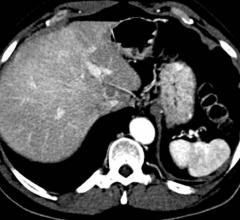

X-ray, or X-radiation, is a form of electromagnetic radiation that can pass through many materials that are opaque to light. They can be used to take images of the inside of the human body.